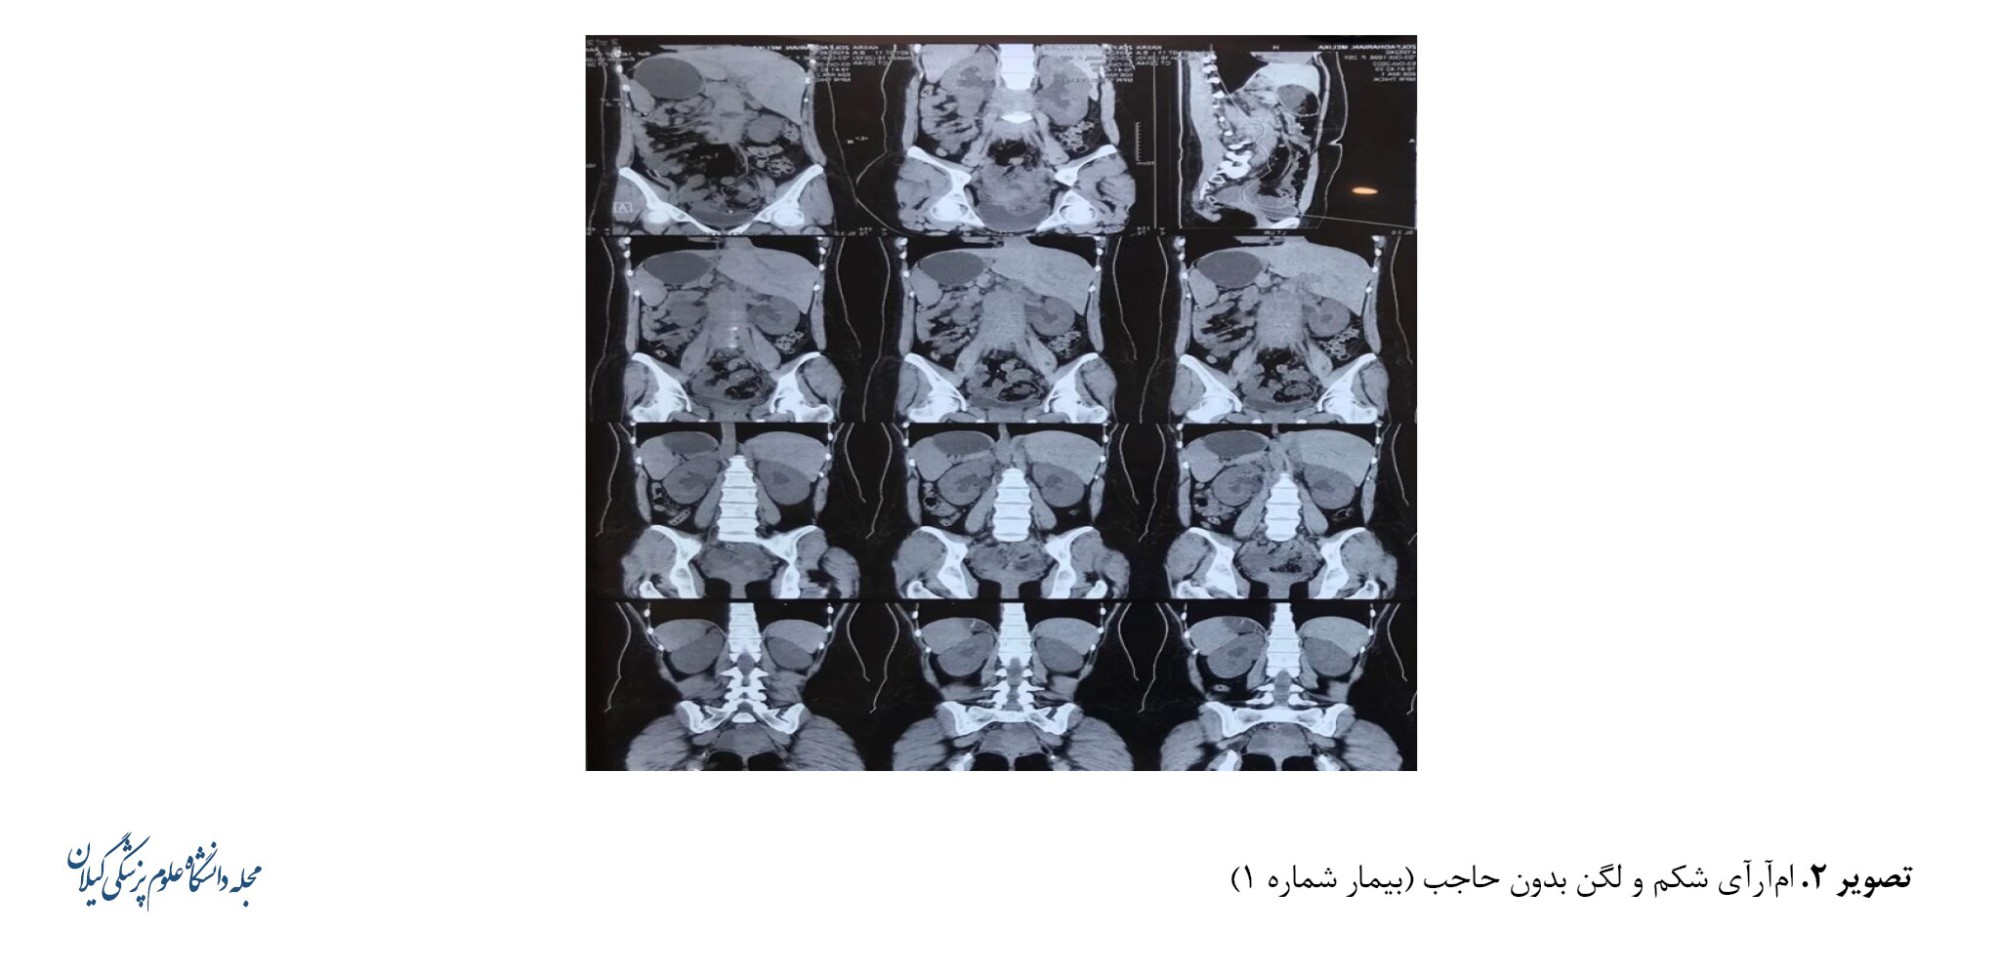

به دلیل افزایش هیدرونفروز و افزایش کراتینین، بیمار تحت نفروستومی دو‌طرفه از راه پوست قرار گرفت. پس از کاهش کراتینین، تصویربرداری رزونانس مغناطیسی شکم و لگن بدون حاجب برای بیمار انجام شد که توده خلفی‌صفاقی در اطراف آئورت و ورید اجوف تحتانی را تأیید کرد (تصویر شماره 2).